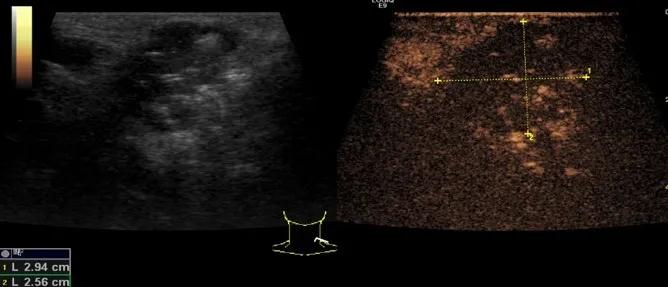

第三例是甲状腺癌患者,双侧甲状腺癌切除术后、碘治疗后一年余效果欠佳,超声显示左颈3区3枚低回声结节,穿刺示甲状腺乳头状癌转移。患者不愿意手术,希望采取局部治疗。对病灶进行液体隔离后采取热消融术,由于淋巴结较小,热消融一分钟左右完全灭活,术后增强影像显示没有脏器充填。

(病例3图例)